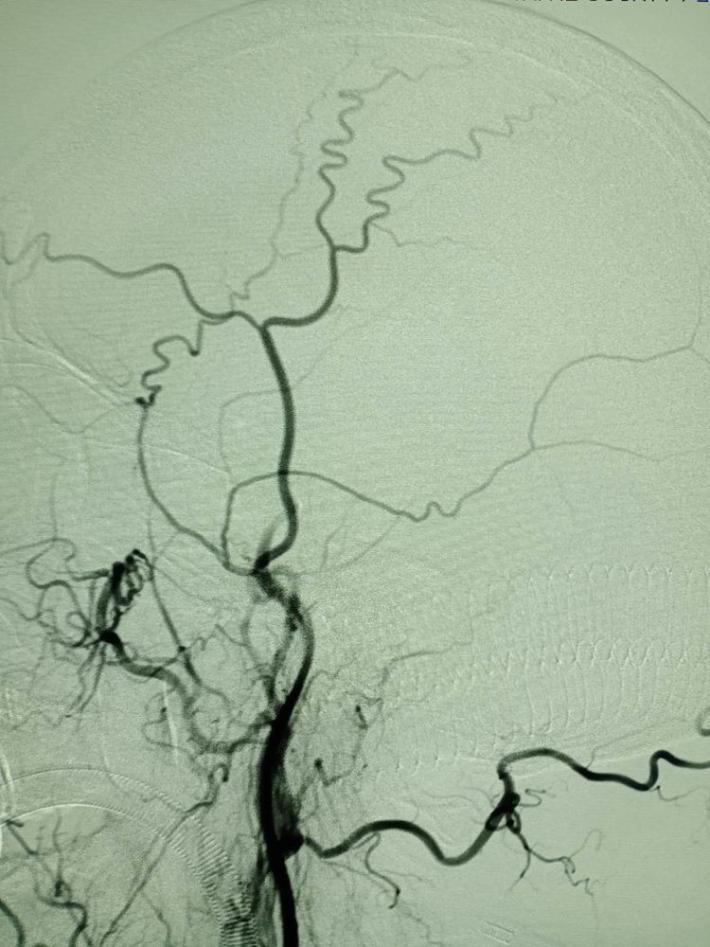

左侧颈总动脉造影提示:左侧大脑中动脉闭塞,考虑责任病变。

左侧椎动脉造影提示:右侧后交通动脉开放,后循环向前循环代偿供血。